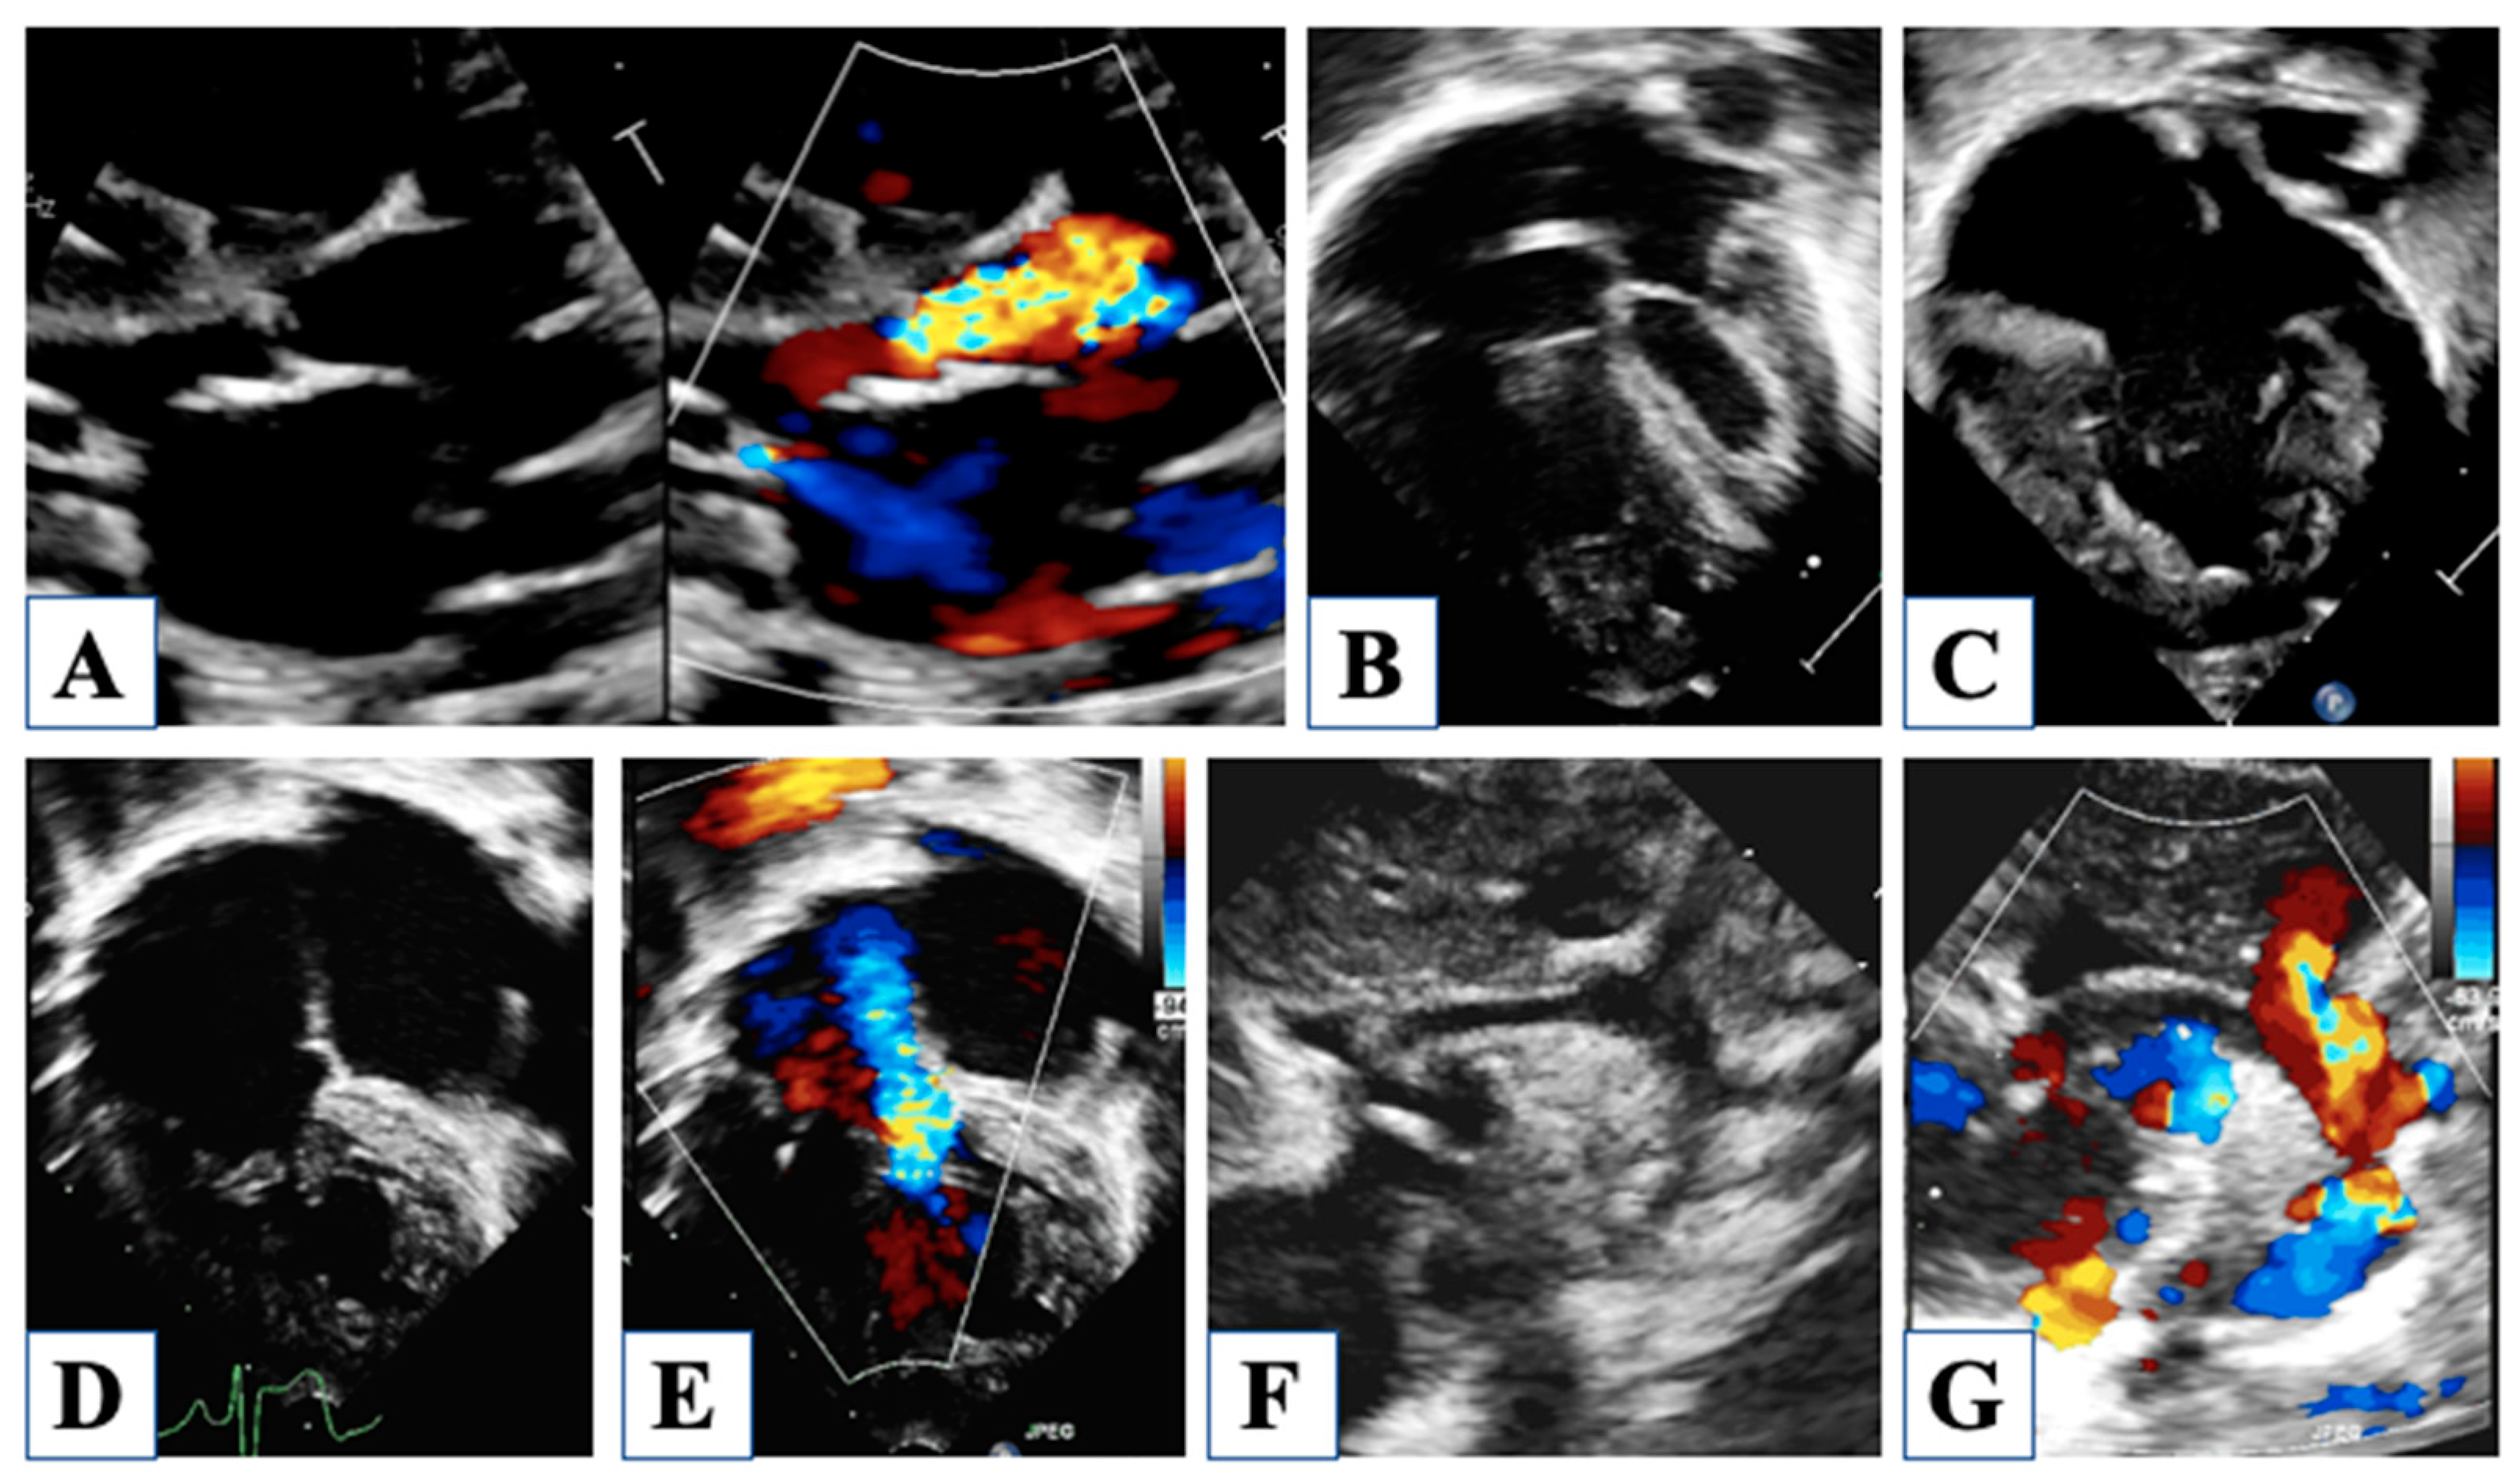

5. After Hybrid Procedure: The Interstage Period

6. After Comprehensive Stage 2 Operation